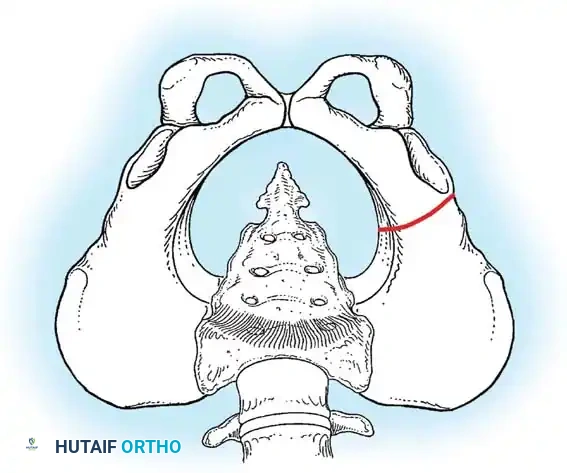

Fig 27-1: Ortolani maneuver for routine screening. The examiner stabilizes the pelvis, places the index and middle fingers over the greater trochanter, and gently abducts the hip.

Diagrammatic representation of the Salter Innominate Osteotomy. Note the complete iliac cut and the placement of the triangular bone graft to redirect the acetabulum.